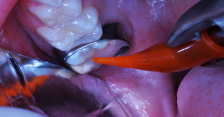

The occlusal-distolingual tooth preparation was completed, and a stainless steel orthodontic band was pressed into place to serve as a matrix (Figure 7). After two 60-second applications of a 5% glutaraldehyde/HEMA desensitizing solution, a self-etching bonding agent was painted on the enamel surfaces. An RMGI bioactive ionic resin-based composite was then injected in two portions (Figure 8), with 10-second light beam exposure between the injections. After the material was injected to overfill, the light beam was applied once more, for 20 seconds (Figure 9). The restoration was then trimmed and finished in the usual manner using large, round diamond burs at slow speed and diamond finishing burs on the axial surfaces (Figure 10). The self-etching bonding agent was then applied as a final glaze, and occlusal contacts were adjusted using articulating paper as a guide.

An RMGI bioactive ionic resin-based composite was injected after a self-etching bonding agent was applied.

Figure 8

Light exposure was applied for 20 seconds.

Figure 9